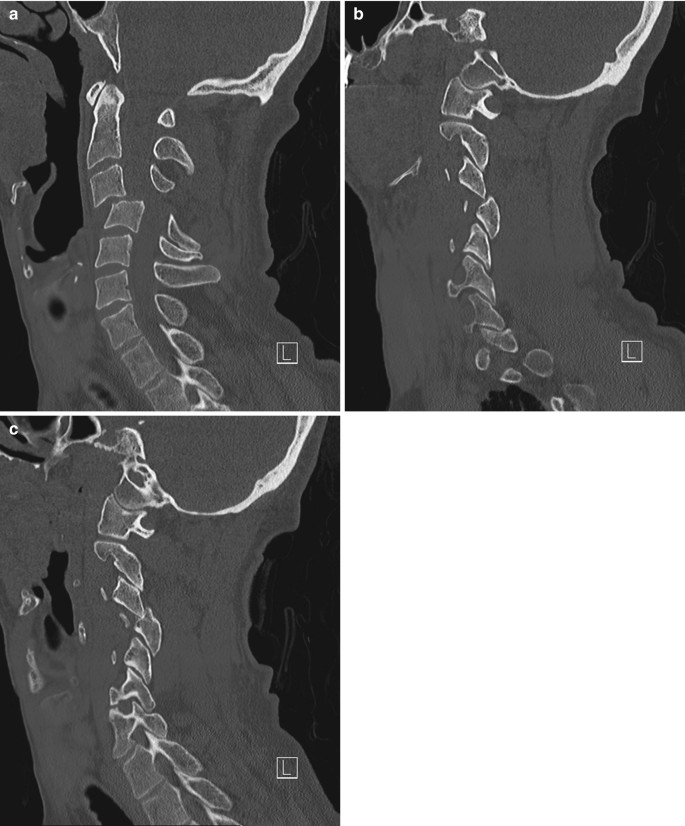

Cervical Spine Fracture Dislocation Springerlink